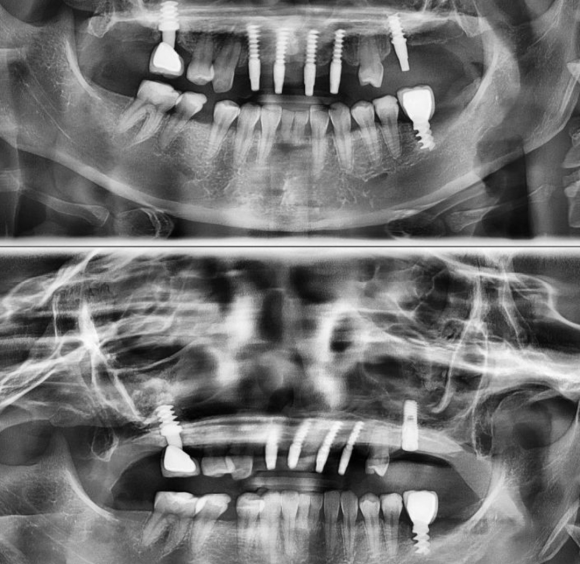

한부모재단 의료지원 재능기부 혜택자. 태어날때부터 선천적으로 치아가 없고 뼈가 발생하지 않아서 음식을 먹기 힘들었는데 금전적 그리고 마음적으로 치료받을 여건이 되지 않았지만 리더스진치과와의 의료비 지원 사업 혜택으로 임플란트와 뼈이식으로 회복. 저희 숭실대 입구역 리더스진 치과는 한달 평균 임플란트 60~1...

한부모재단 의료지원 재능기부 혜택자.

태어날때부터 선천적으로 치아가 없고 뼈가 발생하지 않아서 음식을 먹기 힘들었는데

금전적 그리고 마음적으로 치료받을 여건이 되지 않았지만

리더스진치과와의 의료비 지원 사업 혜택으로 임플란트와 뼈이식으로 회복.

저희 숭실대 입구역 리더스진 치과는 한달 평균 임플란트 60~100개를 꼼수 없이 가장 좋은 재료와 기술로 원칙적으로 식립하는 치과입니다.